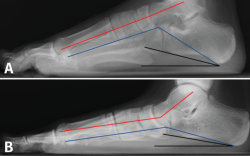

Radiografía dorsoplantar en carga (Figura 5)

Figura 5. Radiografía dorsoplantar en carga. Ángulo Kite (azul). Ángulo C5M (verde). Ángulo del eje del astrágalo y el eje del primer metatarsiano (rojo). Ángulo de descobertura talonavicular (negro).

- Ángulo astrágalo-calcáneo (AC) o de Kite (normal entre 20 y 30°): su aumento es el reflejo de la divergencia AC aumentada en el PPV de componente subtalar.

- Ángulo entre el borde lateral del calcáneo y el eje longitudinal del quinto metatarsiano (C5M): su alteración se correlaciona con la abducción del antepié, siendo su valor normal 0°.

- Ángulo entre el eje del astrágalo y el eje del primer metatarsiano (valores normales de 0 a 5°). Este ángulo es útil para determinar el componente de metatarso aducto. Asociado a una divergencia AC aumentada, orienta a un pie en serpentina o en Z.

- Valoramos la cobertura TN con el ángulo de descobertura TN (valores normales de 10°) o con el porcentaje de descobertura de la cabeza del astrágalo (si > 40%, indica deformidad en abducción severa)(7).

Radiografía lateral del pie en carga (Figura 6)

Figura 6. Radiografía lateral del pie en carga. A: pie normal; B: pie plano. Ángulo de Meary (rojo). Ángulo de Costa-Bartani (azul). Calcaneal pitch angle (negro).

- Ángulo de Costa-Bartani: mide el arco longitudinal medial y está definido por 2 líneas que unen respectivamente los puntos más bajos del calcáneo, el astrágalo y la cabeza del primer metatarsiano, siendo normal entre 125 y 135°. Aumentado en PPV, es una medida del aplanamiento del arco interno.

- Ángulo de Meary (ángulo lateral del astrágalo-primer metatarsiano): su valor normal es entre 0 y 10°. Este ángulo también es una medida del aplanamiento del arco interno y está alterado en los diferentes patrones de pie plano (media de 35°).

- Calcaneal pitch angle (ángulo de inclinación del calcáneo): es normal entre 20 y 30°. Está disminuido en todos los patrones de pie plano, excepto en el patrón de pie plano cavo, que está aumentado.